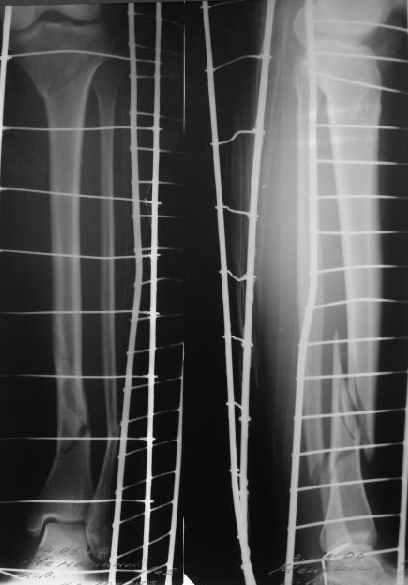

Направили к нам пациентку 35 лет с переломом дистального отдела костей голени.

У нас сделали снимок сзахватом обоих суставов - еще и проксимальный метафиз сломан. Чем бы у вас фиксировали такой перелом? Как его правильно закодировать по классификации АО?